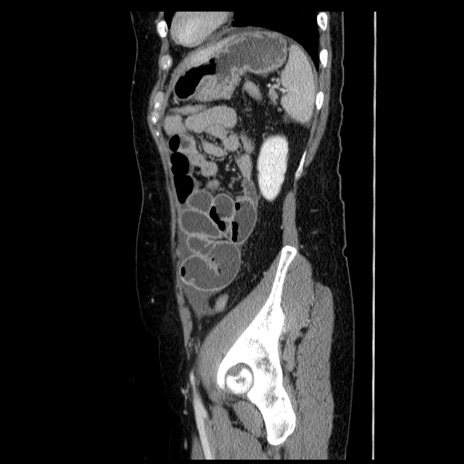

症例6(矢状断像)

【症例】50歳代女性

【主訴】下腹部痛

【既往歴】卵巣癌術後(8年前に当院で卵巣摘出)

【身体所見】 意識清明、腹部:平坦、腸蠕動音→、やや硬、下腹部自発痛・圧痛あり、反跳痛あり、筋性防御なし。

【データ】WBC 16000、CRP 0.01